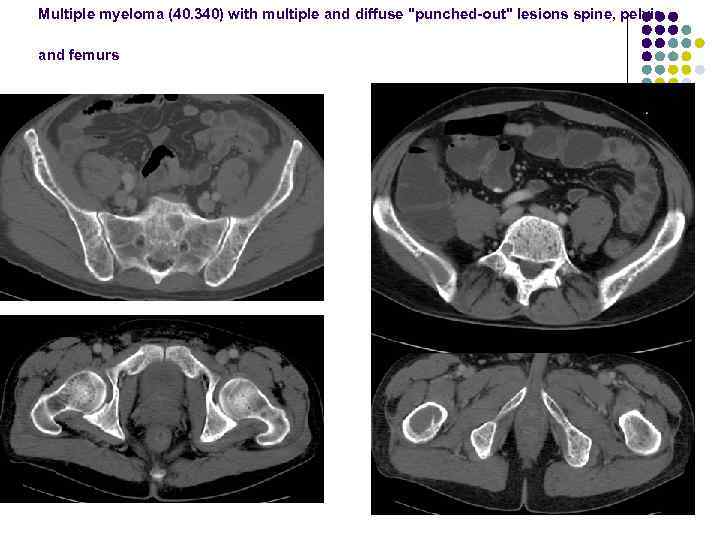

Multiple myeloma (40. 340) with multiple and diffuse "punched-out" lesions spine, pelvis and femurs